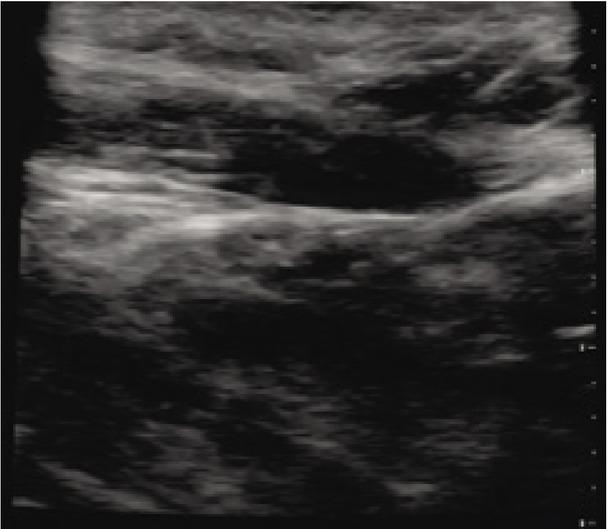

Fig. 3

Long-axis view of second branchial cleft cyst

A 31-year-old female with no past medical history presented to the emergency department with the chief complaint of a “hole” in her neck that had been present since childhood, with no previous workup or diagnosis. The patient described intermittent, clear fluid of varying consistency draining from the site. She denied any recent illness, fever, pain, swelling, numbness, dysphagia, and dysphonia. Her speech was clear without hoarseness. On examination, a small, approximately 2 mm defect in the skin of the right lower neck, located just anterior to the SCM, was present. The skin around the area was normal in color, without erythema or purulent drainage, and was smooth to light palpation, with no mass appreciated on deep palpation (Fig. 1). No cervical lymphadenopathy was present. Cranial nerve examination was within normal limits. A handheld ultrasound system was used to evaluate the area of interest with a single, multi-frequency, capacitive micro-machined ultrasonic transducer (manufacturer: Butterfly IQ). A vascular access setting, roughly equivalent to a high-frequency linear piezoelectric transducer, was used to identify a well-defined, hypoechoic, heterogeneous, cyst-like structure with a thin, enhancing rim and moderate posterior acoustic enhancement that had a short axis length greater than 0.83 cm × 0.63 cm, and was approximately 0.4 cm deep to the skin at the most superficial aspect (Fig. 2 and Fig. 3). Color flow Doppler did not demonstrate any blood flow within the structure. After thorough ultrasound evaluation, a fistula tract was unable to be visualized; however, given the history of secretions and the presence of an obvious skin defect overlying the structure, a fistula tract to the underlying structure was felt to be likely present. Given the history, physical examination findings, and point-of-care ultrasound imaging, the diagnosis of a second branchial cleft sinus was made. The patient provided written consent for images and publication of this case.